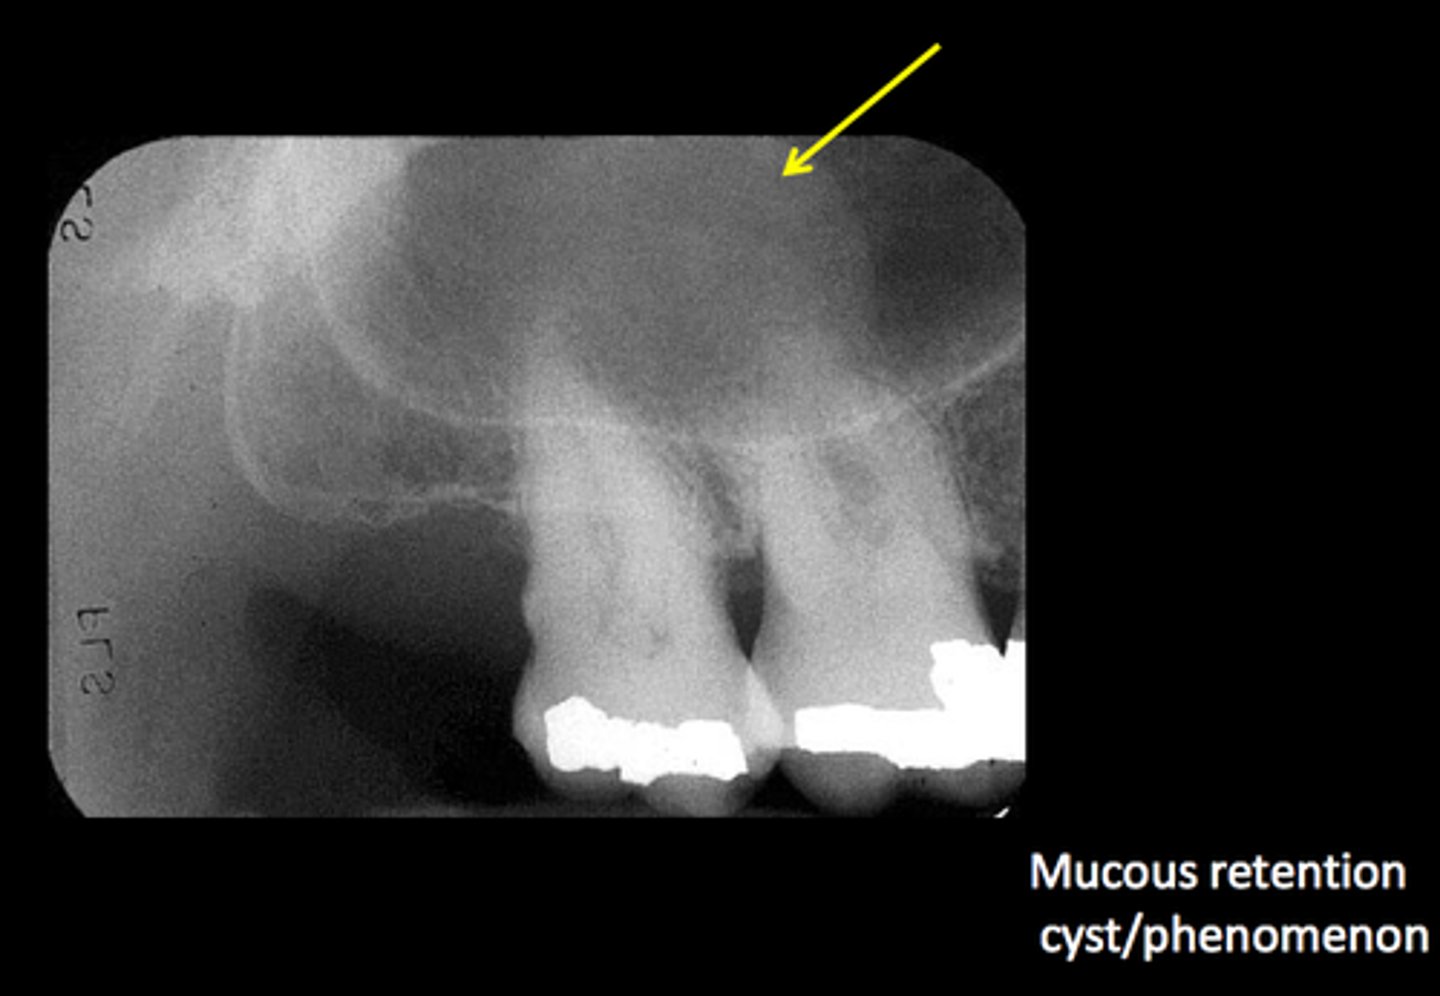

Radiopacity on a pan in sinus. What is it?

Mucous retention cyst in the maxillary sinus